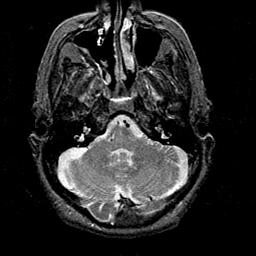

Alzheimer's disease MR T2-weighted -- Slice #10

[Home][Help][Clinical][Tour 1][Tour 2] Slice 10